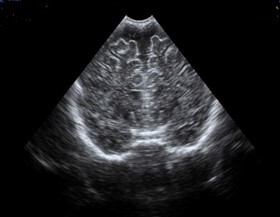

Neonatology Wide Subarachnoid Space 2 Image